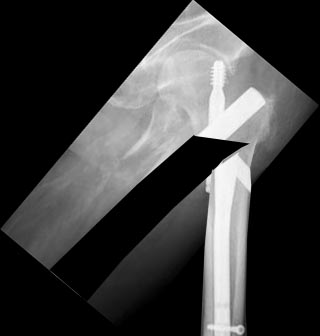

Здесь был чрезвертельный перелом, не меж- или подвертельный, поэтому

компрессия по оси шейки вполне пригодится. Медиализировать диафиз

действительно не надо, так что лучше взять пластину без

медиализированной  диафизарной части.

Здесь надо хорошо вальгизировать проксимальный отдел, поскольку диафиз

смещен проксимально - вот так бы неплохо сделать, как на картинке. И 130

градусная пластина подойдет для этого гораздо лучше, 95 градусную тут

вряд ли для такой коррекции можно разместить.